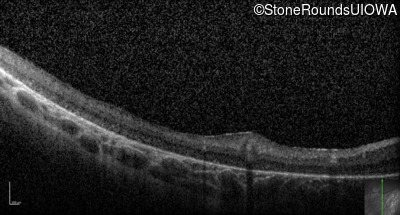

Optical Coherence Tomography - Right -

No Light Perception

Exemplar

Expanded OCT Stack

×